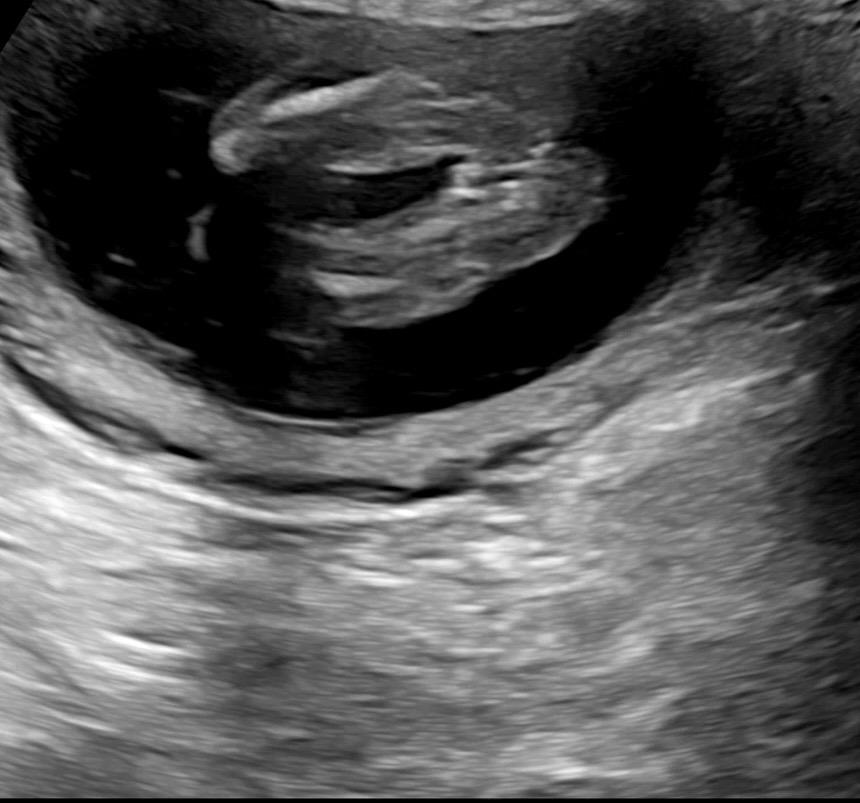

15주 6일차 병원 다녀왔는데 아가가 다리꼬아서 있느라고 자세히는 못봤어요 선생님 말씀으론 거의 딸 같다고 하시는데 다른분들 보시에도 딸 같나요?